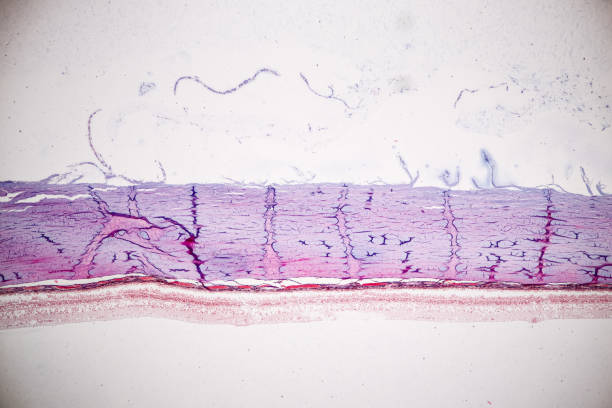

대표적으로 녹내장의 원인은 안압상승으로 인해 시신경이 손상원인이 녹내장 질환을 발생하게 합니다. 나이가 들면 노화가 진행됨으로써 눈의 각 부분 조절능력이 떨어져 안구 내의 안압이 높아지면서 이로 인해 뇌로 연결되는 시신경이 손상되면서 녹내장이 발생됩니다. 녹내장이 나타나면 시야가 좁아지면서 심하면 실명할수도 있습니다. 녹내장을 유발하는 대표적인 원인에 대해 알아보겠습니다.

녹내장 원인 두 번째는 고도 근시입니다. 고도 근시는 안구의 길이가 상대적으로 길어진다고 알려져 있습니다. 안구의 길이가 길어질수록 안구와 연결되는 시신경을 지지하는 구조가 얇아지고 힘을 덜 받게 되는데 이로 인하여 구조가 약해지면서 안압이 점차 시신경으로 전달되어 녹내장을 유발할 수 있습니다.

녹내장은 안통과 두통뿐 아니라, 시신경 손상으로 인한 안구 충혈을 유발할 수 있습니다. 만일, 이러한 안구 충혈이 지속해서 발생하는 경우 녹내장을 의심해볼 수 있습니다.